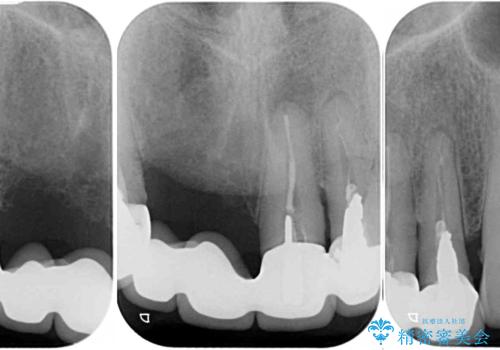

- 前歯のブリッジのせいで話しにくく、金属の縁などが露出して見栄えが悪いので、作り直したいとのことで来院された患者様です。

土台となる歯は根管治療の結果が良好ではないため、根管治療からやり直しをした後、オールセラミックブリッジにて補綴することとしました。